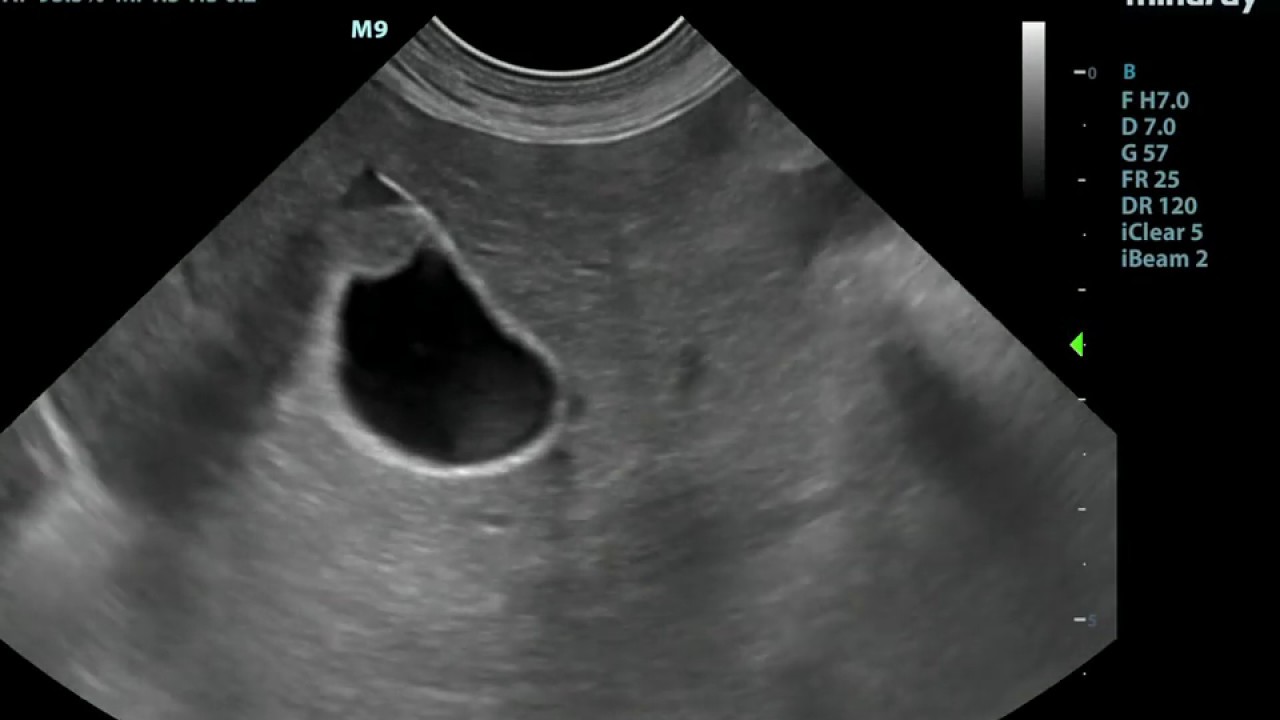

Small Animal Ultrasound . Access the atlas of small animal. Learn how to scan the abdomen of dogs and cats using a systematic pattern and basic ultrasonography principles. Welcome to our newest series of articles on small animal abdominal ultrasonography. Learn, exchange and collaborate on small animal ultrasonography with videos, 3d animations and exercises. The first 4 articles in the series provide an overview on the. This article covers the liver, gallbladder, and bile ducts in dorsal recumbency. We really felt the need to better support those relying on clinical ultrasound to maximise small animal patient outcomes. Build on your existing ultrasound knowledge and unlock your full potential.

Small Animal Ultrasound Welcome to our newest series of articles on small animal abdominal ultrasonography. The first 4 articles in the series provide an overview on the. We really felt the need to better support those relying on clinical ultrasound to maximise small animal patient outcomes. Welcome to our newest series of articles on small animal abdominal ultrasonography. Access the atlas of small animal. Learn how to scan the abdomen of dogs and cats using a systematic pattern and basic ultrasonography principles. Build on your existing ultrasound knowledge and unlock your full potential. This article covers the liver, gallbladder, and bile ducts in dorsal recumbency. Learn, exchange and collaborate on small animal ultrasonography with videos, 3d animations and exercises.

Practical Small Animal Ultrasound AFAST Scanning Techniques Clarius Small Animal Ultrasound This article covers the liver, gallbladder, and bile ducts in dorsal recumbency. Access the atlas of small animal. The first 4 articles in the series provide an overview on the. Welcome to our newest series of articles on small animal abdominal ultrasonography. Learn how to scan the abdomen of dogs and cats using a systematic pattern and basic ultrasonography principles.. Small Animal Ultrasound.